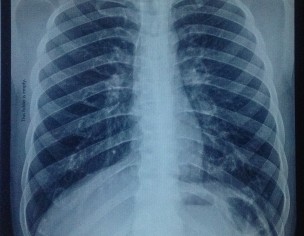

Request to radiologists to examine the attached chest e x-ray image, if it is clear or has any kind of abnormality. If there is ANY kind of abnormality please highlight it. My friend has to go abroad for job search.

Both lungs normal

Cardiac size with in normal limits .

Both CP angles , hila and mediastinum are normal.

NORMAL CHEST XRAY

Respectable Dr. Thank you for your response. One question i want to ask, can you please explain the (dot type) spot located at lower right lung, under 8th or 9th rib. Either it's any kind of abnormality/considerable thing or should not worry about it?🙂

And if it is any kind of problem should patient meet any Pulmonologist for this?

Both lungs normal, airway central, normal cardiac silhouette, clear CP angles, central mediastinum and hila.

Normal chest x-ray

Thank u so much for ur response. One more question i want to ask is that there is a tiny (dot type) spot located at lower right lung under the 8th or 9th rib, what is this? Either it's any kind of abnormality or any thing else? Should i worry about it?